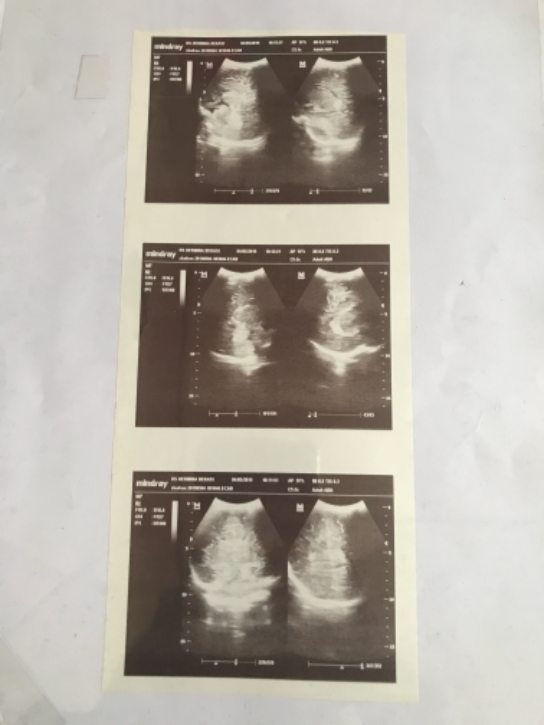

hasil usg jantung

2021-12-20 09:39:57

usg otak

2021-12-20 09:30:32